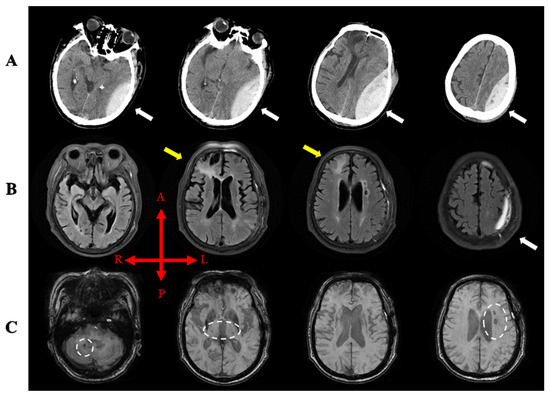

2. Case Report